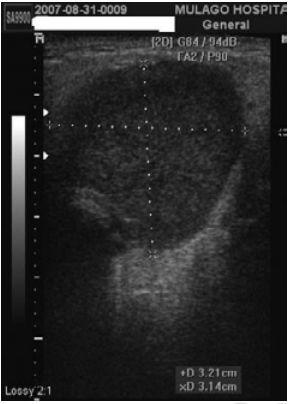

Burkittov limfom predstavlja vrlo agresivan ne-Hodgkinov limfom, a prema klasifikaciji Svjetske zdravstvene organizacije postoje tri kliničke varijante tog limfoma: endemičan, sporadičan i udružen s imunodeficijencijom (8). U bolesnika zaraženih HIV-om postoji dva puta veći rizik za razvoj Burkittovog limfoma i on čini 5-40% ne-Hodgkinovih limfoma u toj skupini bolesnika (8). Žarišni oblik bolesti prikazuje se kao uvećan, hipoehogen intraparotidni limfni čvor koji može davati stražnju atenuaciju ultrazvučnog snopa (Slike 5. i 6.). Difuzni oblik je nespecifičnog izgleda pri čemu je žlijezda u cijelosti uvećana i ne može se razlikovati od kronične granulomatozne upale.

Slika 5.: Otok parotidne žlijezde kod limfoma

Slika 6.: Ultrazvučni prikaz ne-Hodgkin limfoma u parotidnoj žlijezdi